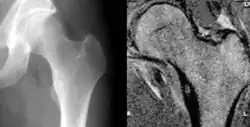

O diagnóstico é suspeitado pela verificação da presença do nicho em um dos métodos de imagem: raio-X, cintilografia óssea, ou tomografia computadorizada. A localização do nicho, por ser uma estrutura muito pequena pode ser difícil mesmo com exames de imagem. A ressonância magnética pode trazer confusão diagnóstica ao demonstrar uma área de edema ósseo.